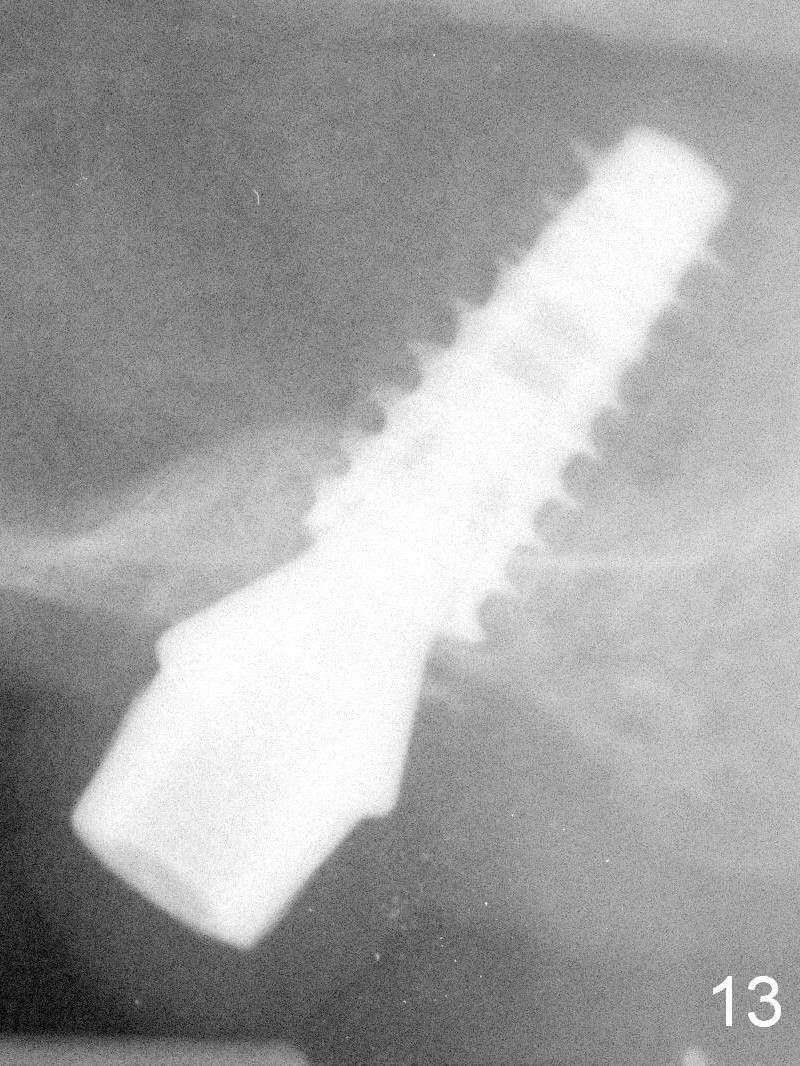

The bone density in the mesial socket appears to increase and becomes more homogenous 3 months postop (Fig.13).  Impression is taken for final restoration.